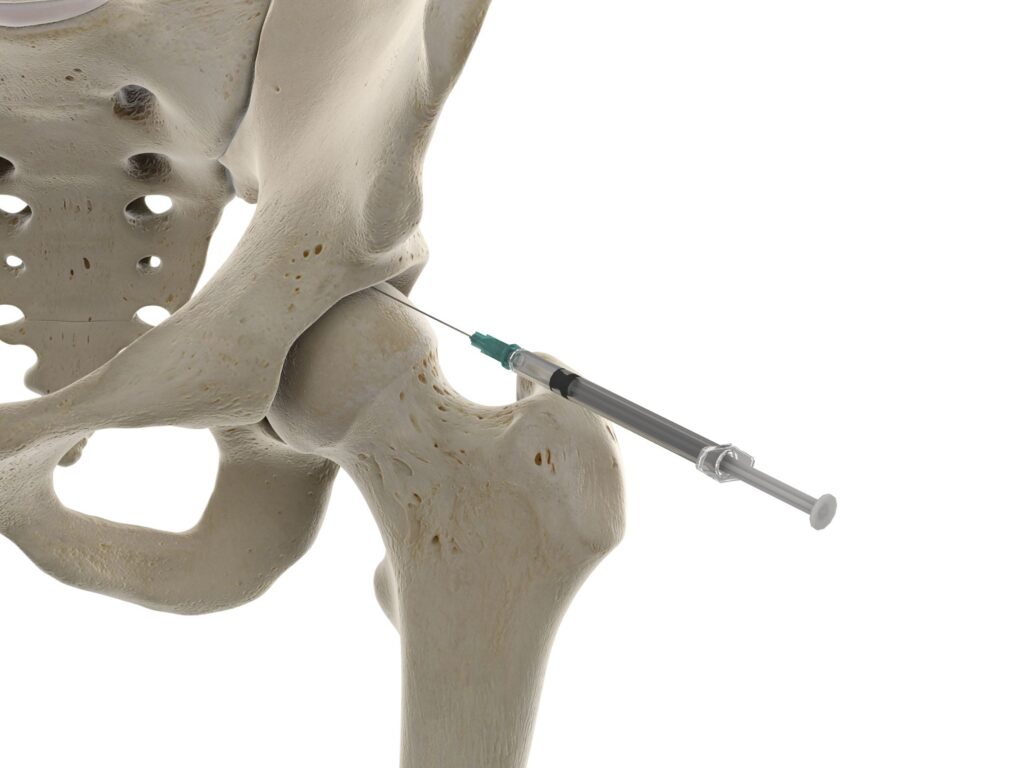

Infiltração no Quadril: Resolve?

A infiltração pode até trazer alívio temporário, mas não resolve o problema. É como desligar o alarme de um carro sem consertar a falha que fez ele disparar. A dor pode desaparecer por um tempo, mas a causa ainda estará lá, esperando para reaparecer.

Para um resultado duradouro, você precisa de um plano de tratamento que atue na raiz do problema. E os movimentos terapêuticos inteligentes são a melhor estratégia para isso.